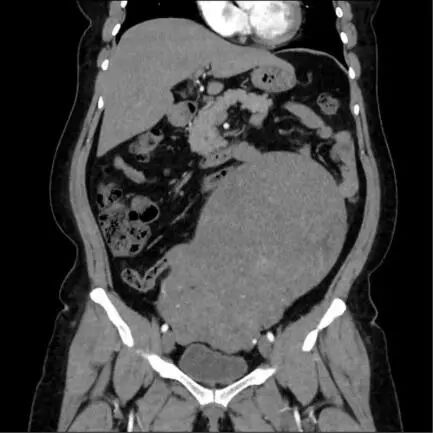

患者李女士(化名)曾于2015年因子宮肌瘤在外院接受腹腔鏡下子宮肌瘤剔除術,術后因自覺恢復良好,未堅持定期復查。直至近期腹部受到輕微撞擊后出現(xiàn)持續(xù)腹痛,才來潛江市中心醫(yī)院就診。經(jīng)超聲檢查發(fā)現(xiàn),其子宮形態(tài)失常,增大如孕7月大小,肌壁間可見多個大小不等的肌瘤樣占位,其中最大者截面約110mm×90mm,因患者體型偏胖,此前并未察覺腹部異常,結合超聲結果門診醫(yī)生建議盡快住院手術。

鑒于腫瘤體積巨大、生長速度不確定,且患者有肌瘤手術史,為排除子宮肉瘤等惡性病變可能,婦科主任周筠予以高度重視,迅速啟動多學科會診機制。結合影像學特征與臨床指征進行綜合評估,并制定了個體化的手術方案與應急預案,確保診療過程穩(wěn)妥周全。